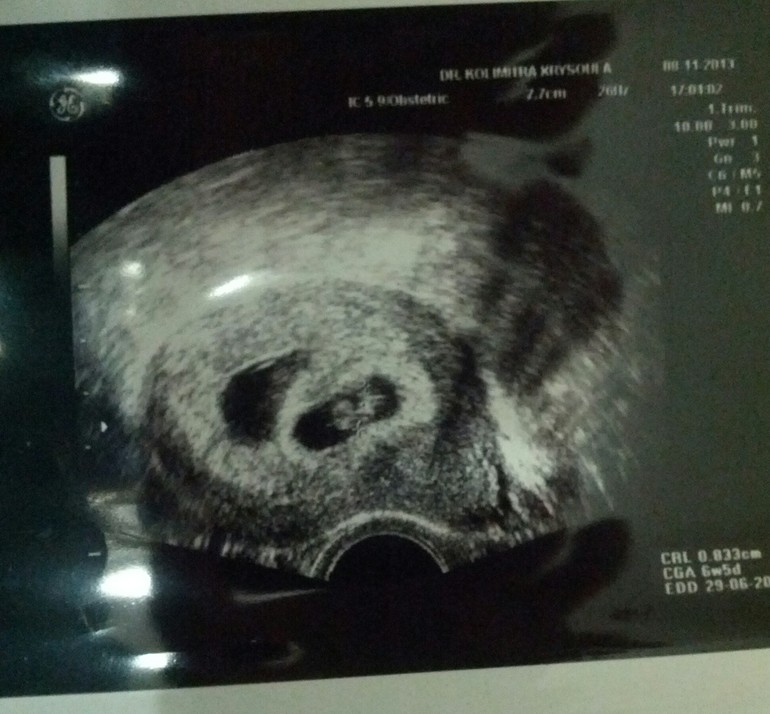

Мои головастики))

Я буду мамой двойняшек! Принимаем в наши рядыУра!

Пузожителей двое! Сердечки бьются сильно у обоих!!!

Головастик тот что поменьше, проявил характер и поднялся в подобающее ему место! Разница хоть и есть (5-6 дней), но для близнецов она - нормальное явление.